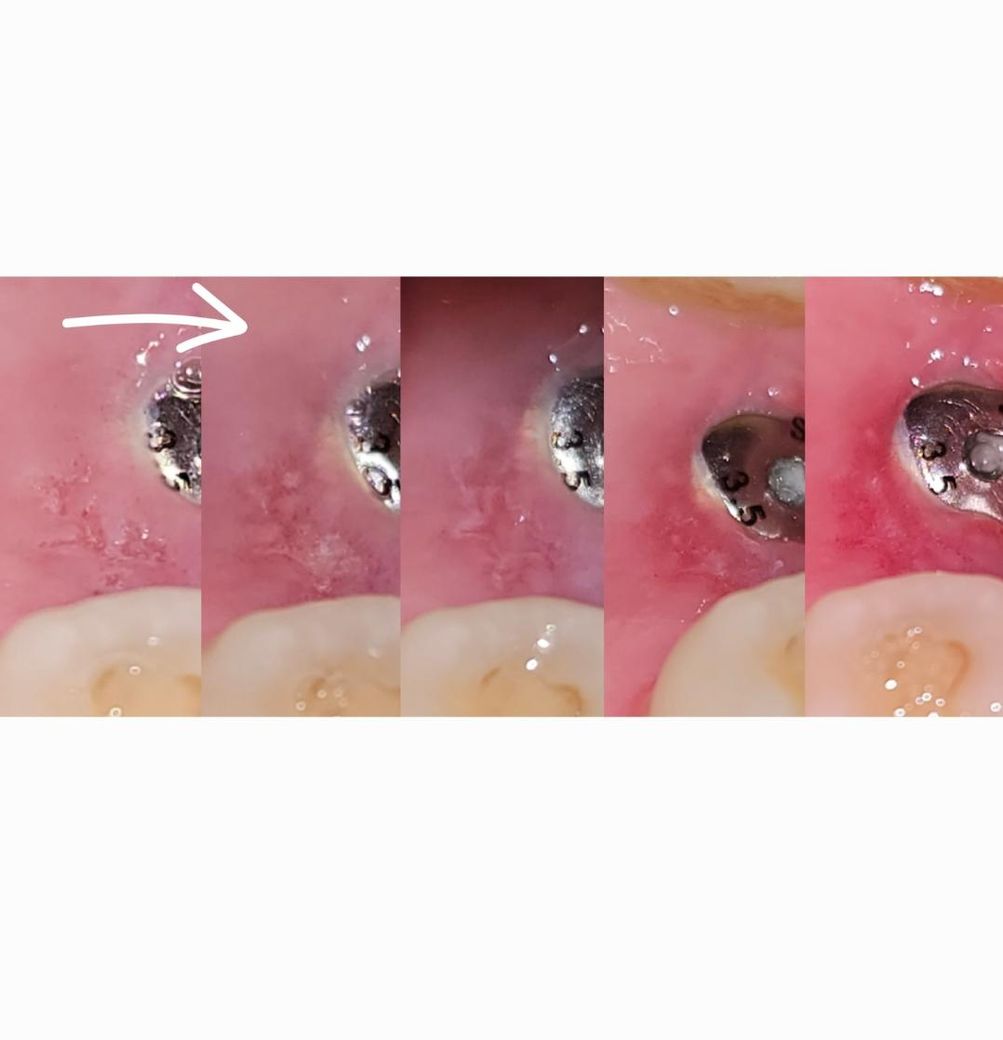

다음 사진은 왼쪽(첫날)부터 오른쪽(오늘)까지 시간순으로 정리 한 것인데

이게 낫고 있는건지 안좋아지고 있는건지 모르겠어요.

사진을 살펴보니 낫고 있는 과정으로 보입니다.

통증이 점차 줄어들고,궤양이 점차 작아지고 주변 조직이 더 건강한 색으로 변한다면 치유 과정 중일 가능성이 높습니다.